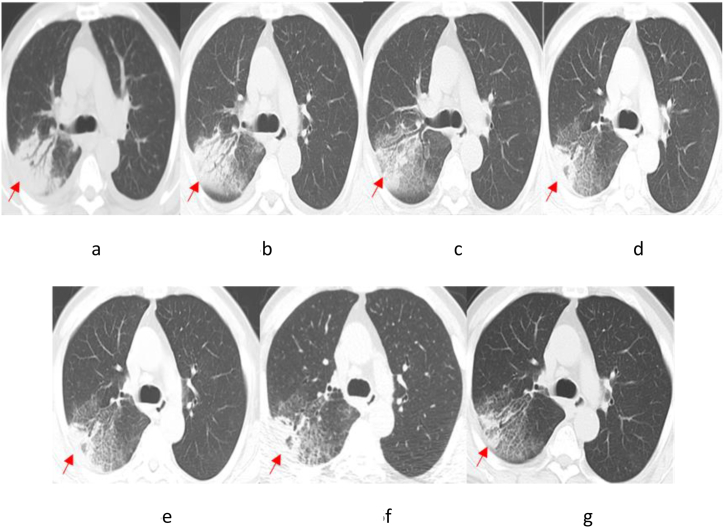

Patient 4 had an underlying condition of coronary atherosclerotic heart disease. Following admission, Patient 4 was treated with moxifloxacin for 2 days, yet without any improvement in the condition. Then, the patient was given an altered therapy of piperacillin-tazobactam combined with levofloxacin for two days. Unfortunately, the patient suddenly developed acute Myocardial infarction and died. After death, the patient was diagnosed with pneumonia caused by TW infection following a discussion by an expert group (Chest CT results in Fig. 5). Patient 5 had underlying conditions of MDS and diabetes. After admission, Patient 5 was initially treated with moxifloxacin for 2 days and subsequently administered piperacillin for 15 days, yet without significant improvement in lung lesions. Subsequently, the treatment plan was modified by the attending physician to long-term treatment with levofloxacin combined with doxycycline, resulting in a gradual improvement in the lung lesions (Fig. 6(a–g)). After a retrospective discussion by the expert group, the patient was confirmed with pneumonia caused by TW infection, and was recommended to be hospitalized to receive the standard treatment plan for WD. However, the patient declined hospitalization, still has a paroxysmal cough at present.

Fig. 6.

Chest CT Scan of Patient 5 (First line: the dates from left to right: July 15, 2022 (a); July 25, 2022 (b); August 1, 2022 (c); and August 23, 2022 (d). Last line: the dates from left to right: September 4, 2022 (e); October 12, 2022 (f); and November 9, 2022 (g)). The arrowhead shows the focus.